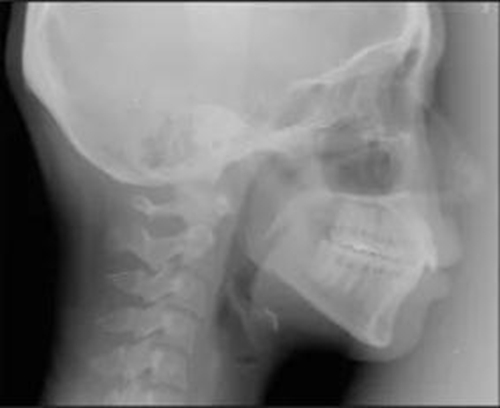

頭側(cè)分析提示為骨性安氏II類(lèi)(ANB,8.4°;Wits,3.6mm),高角(SN-MP,44.9°),上頜切牙略舌傾(U1-SN,96.2°),下頜切牙略舌傾(IMPA,88。3°)(圖2;表)

治療后頭側(cè)數(shù)據(jù)提示:無(wú)明顯骨性變化(上頜SNA82.1°,下頜SNB74.9°),上頜前牙得到內(nèi)收,略舌傾,頦部前后位置無(wú)明顯改變,仍未凸面型(圖8,表)。將治療前后圖像重疊后結(jié)果如(圖8及圖9),24月后隨訪結(jié)果見(jiàn)圖10.